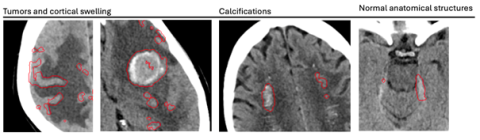

La cohorte rétrospective comprenait 725 scanners cérébraux réalisés entre 2012 et 2024 dans deux hôpitaux universitaires brestois, incluant 60 % de cas d’HIC, 25 % de diagnostics différentiels (tumeurs, malformations vasculaires, calcifications, artefacts) et des examens normaux. La vérité terrain reposait sur une lecture indépendante et en aveugle de trois lecteurs parmi cinq, avec consensus majoritaire. Les lésions ont été localisées par annotations manuelles, permettant une analyse exploratoire des sous-types basée sur la concordance spatiale entre les segmentations de l’IA et les annotations de référence, avec des critères stricts de validation : un sous-type n’était validé que si toutes les lésions correspondantes étaient détectées (voir image 2).

Image2 clotide ruesh.png

Image 2 : Illustration de la méthodologie utilisée pour l’analyse de détection des sous-types basée sur la concordance spatiale – à gauche, les « bounding boxes » correspondant à la vérité terrain et à droite la segmentation des contours générée par l’IA. Dans cet exemple, le sous-type IPH a été considéré comme un vrai positif (TP) et le sous-type IVH comme un faux négatif (FN).